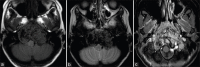

Giant cell reparative granuloma (GCRG) is a benign nonneoplastic granulomatous lesion and is rare in the cranial bone. We present a pediatric case of this lesion arising from the condyle and lower clivus. A 9-year-old girl presented with slowly progressive hoarseness and dysphagia. She showed left glossopharyngeal, vagus, and hypoglossal nerve palsy. An osteolytic lesion around the lower clivus and condyle joint was accompanied by deformation of the craniovertebral junction. An endoscopic endonasal approach was used to decompress the cranial nerve and confirm the pathological finding. The lesion around the condyle was not resected to preserve occipito-cervical stability. The residual lesion has been observed carefully for 6 months, and regrowth has not occurred. GCRG is a rare granulomatous lesion in the cranial bone. This case is the first report of a pediatric clival GCRG. Treating pediatric GCRG may be helpful.